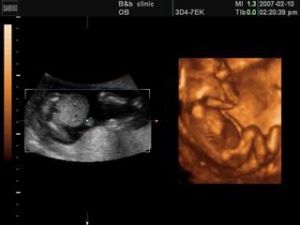

胎照在上海市第一婦嬰保健院浦東分院的介紹手冊上,“服務特色”一欄下有一項為:“四維彩照——通過影像,您可以看到寶寶的一顰一笑,為您寶寶留下人生第一張照片。”諮詢服務台工作人員表示,這樣的影像拍照需孕婦自己提出,一般安排在做彩超檢查時同時做,至於時間長短則要看寶寶的配合情況。

在上海美華婦兒服務中心介紹手冊上,也有類似項目。這裡提供胎兒立體影像拍攝,可以製作成DVD保存。一次四維彩超費用需2000多元,可免費刻盤一張,如需另外刻盤,則每張收費300元。

長寧區婦幼保健醫院B超前台護士表示,為寶寶拍照的B超需要單獨做一次,一張光碟360元,所需時間則要看寶寶的配合情況而定。

超音波檢查本來是孕婦常規檢查手段,但現在越來越多的準媽媽們藉助這一檢查為寶寶拍照。對此,超聲科專家認為,如果沒有異常,整個孕期做3~4次超音波檢查即可。彩超照射胎兒某個部位時間較長的話,可能會給胎兒帶來潛在的傷害。畢竟,超音波是一種醫學程式,而非照相的選擇。世界衛生組織早在1982年就已建議:只有在醫學上具有明確理由時,才可對人體使用診斷超聲;不應以商業和實驗為目的輻照人體,特別是輻照孕婦。

那么在做B超的同時進行拍照按理這樣不存在多做一次的風險,但為了拍到寶寶的臉或其他部位,B逾時間長短和拍照次數都難以把握,與正常B超檢查相比明顯需要更多一些時間。